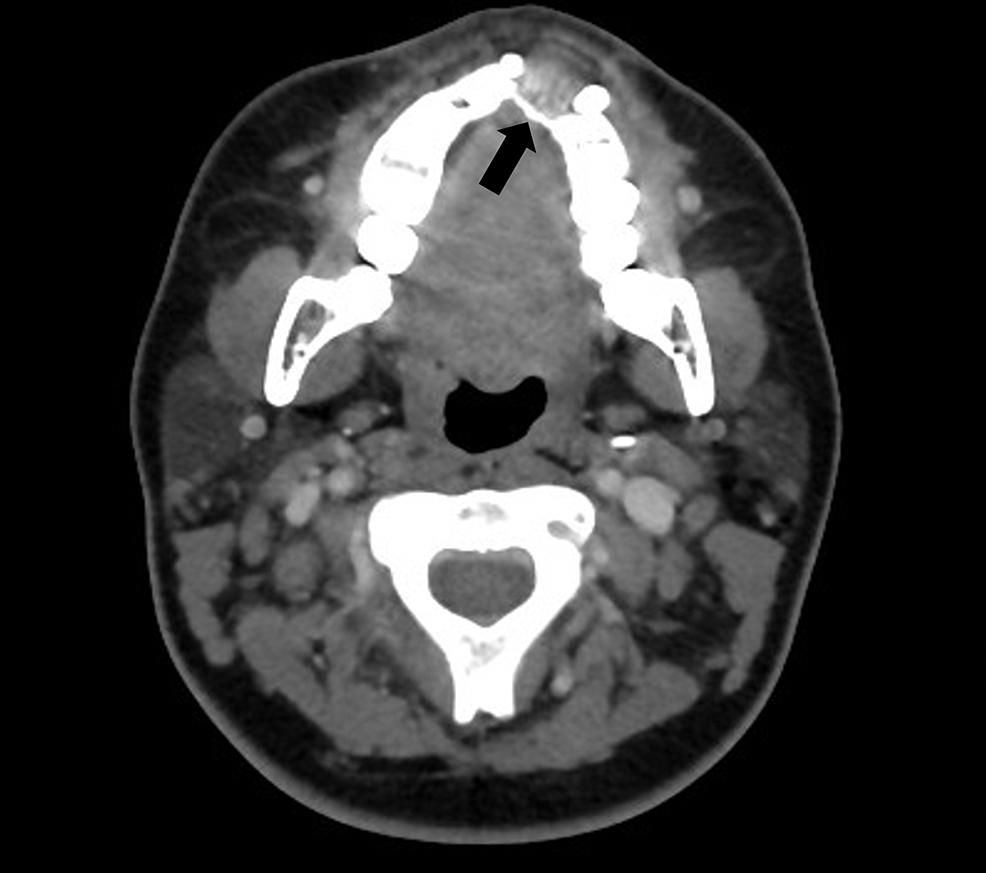

Locally advanced maxillary on a 48yearold male. Download Scientific Diagram Maxillary Osteosarcoma Radiology the head and neck, commonly the skull base, maxilla, nasal cavity, and larynx, is involved in. in comparison with the osteosarcoma affecting the metaphysis of the long bones, maxillary lesions tend to occur in the third or fourth decades of. osteosarcoma (os) is a malignant mesenchymal tumor, which. osteosarcoma (os) is the second most common primary. Maxillary Osteosarcoma Radiology.